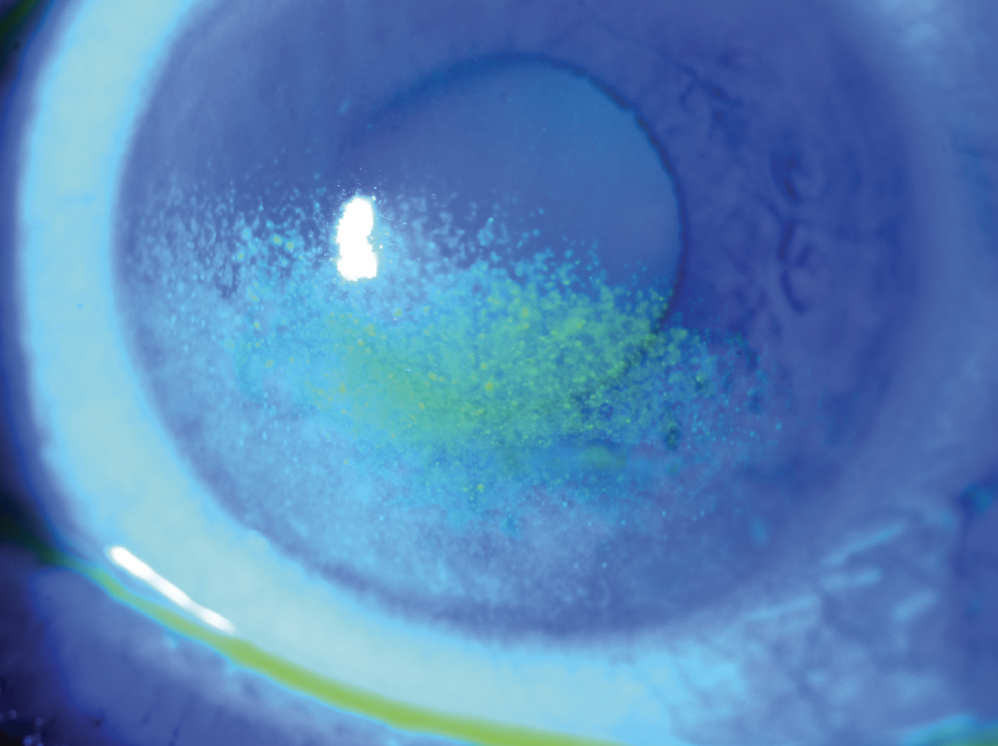

Dry Eye Assessment

Dry eye syndrome is a common condition where the eyes do not make enough tears, or the tears evaporate too quickly. This leads to the surface of the eyes drying out and becoming inflamed. Dry eye happens mostly as part of the natural ageing process but can also be associated with certain general health conditions, smoking, medication and prolonged use of your computer or smartphone.

After thoroughly assessing your eyes, we will guide you through the different types of drops and gels that can help your eyes feel more comfortable. In addition, we will discuss further measures like heated eye masks and eyelid hygiene products, which are also very beneficial in the management of dry eye symptoms.